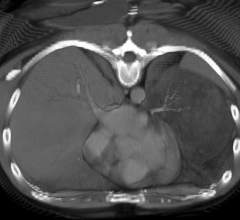

Computed tomography (CT) systems use a series of X-ray images to create an image volume dataset with slices that can be manipulated on any plane using advanced visualization software. The section includes computed tomography scanners, CT contrast agents, CT angiography (CTA and CCTA), CT perfusion, spectral CT (dual-source CT), and iterative reconstruction dose reduction software.

This is an example of a COVID-19 (SARS-CoV-2) positive patient's lung computed tomography (CT) scan. The video scrolls ...